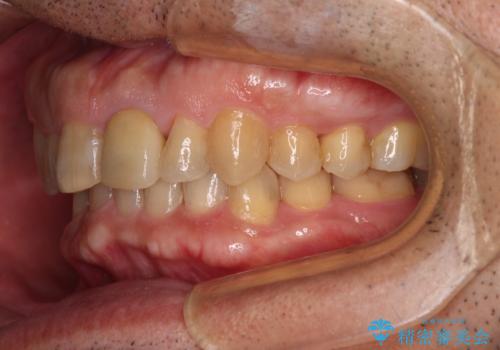

下顎は左右1本ずつ小臼歯が欠損しており、右側にはやや大きな欠損がありました。

欠損により下顎歯列は相対的に小さく、上顎に深く咬みこんでしまうディープバイトとなっていました。

咬合力が強く、インビザラインのみではディープバイトを改善することができず、半年間ほどワイヤー装置による矯正治療を行いました。

インプラントの埋入は矯正治療中に行い、矯正治療後はインプラント上補綴および、前歯のセラミック治療を行いました。